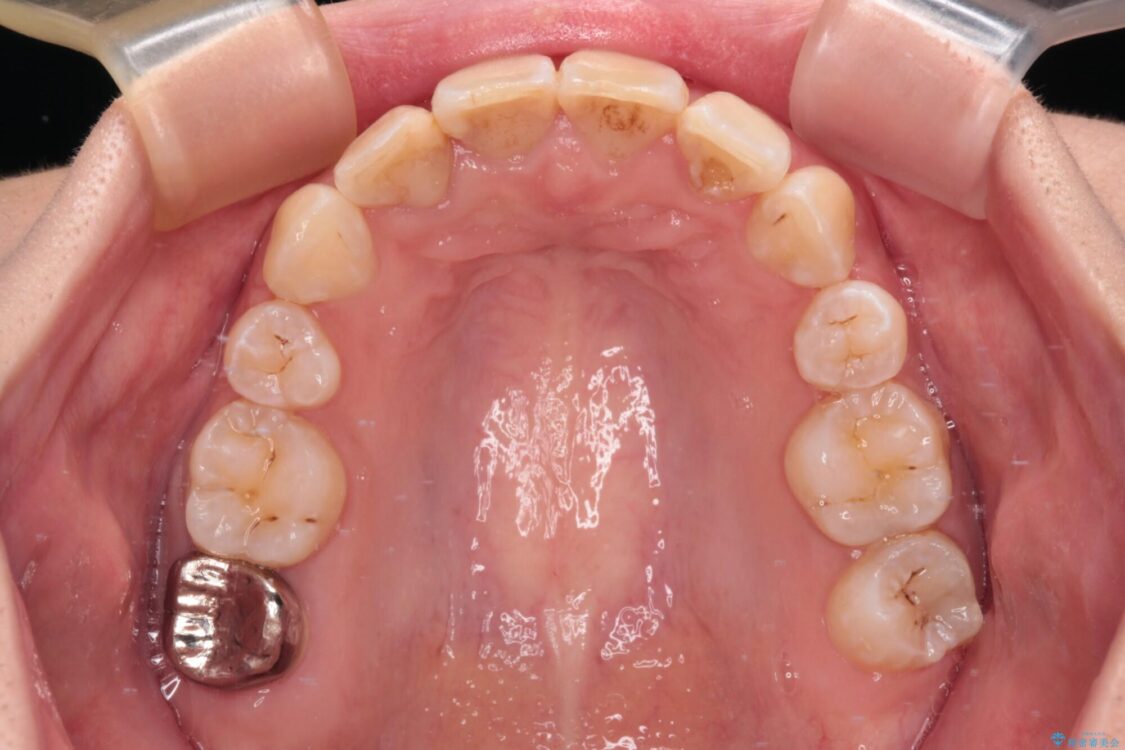

治療後

• デコボコと深い咬み合わせ ワイヤー装置での抜歯矯正 治療後画像

治療後について

咬み合わせが深く、そのままでは上顎の抜歯スペースが閉じきらない可能性があったため、治療初期から深い咬み合わせを改善させるように試みました。

実際にはなかなか改善されず、当初予定よりも治療期間がやや長期化してしまいました。